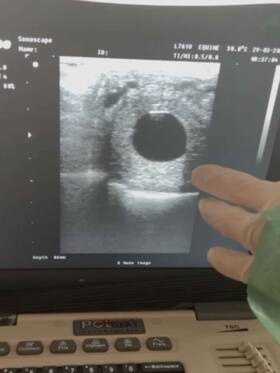

| - Ostatnimi czasy na naszym kanale można było zobaczyć filmiki z badań klaczy w różnym zaawansowaniu ciąż. Porównywałam je między sobą żeby pokazać różnice. Dziś dodaję ostatni z tej seri film. Super jest oglądać jak się rozwijają płody, zobaczyć oko czy

|

| - Pierwsza źrebna klacz w tym sezonie- Shavalou (So Unique x Hohenstein). 14 dni temu została zainseminowana ogierem Dimaggio Black (Dimaggio x Furst Heinrich). Zapraszamy Was do obejrzenia filmiku z jej badania, chociaż może być trudno skupić się na czymś